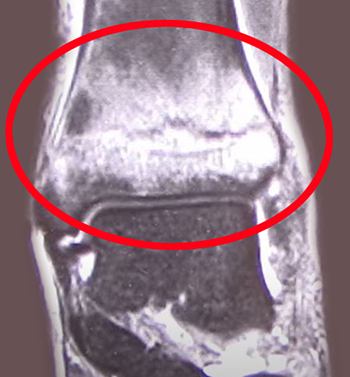

骨挫傷は、レントゲンやCTでは骨の異常は発見できないことが多く、MRIで骨の内部の内出血の有無を調べます。